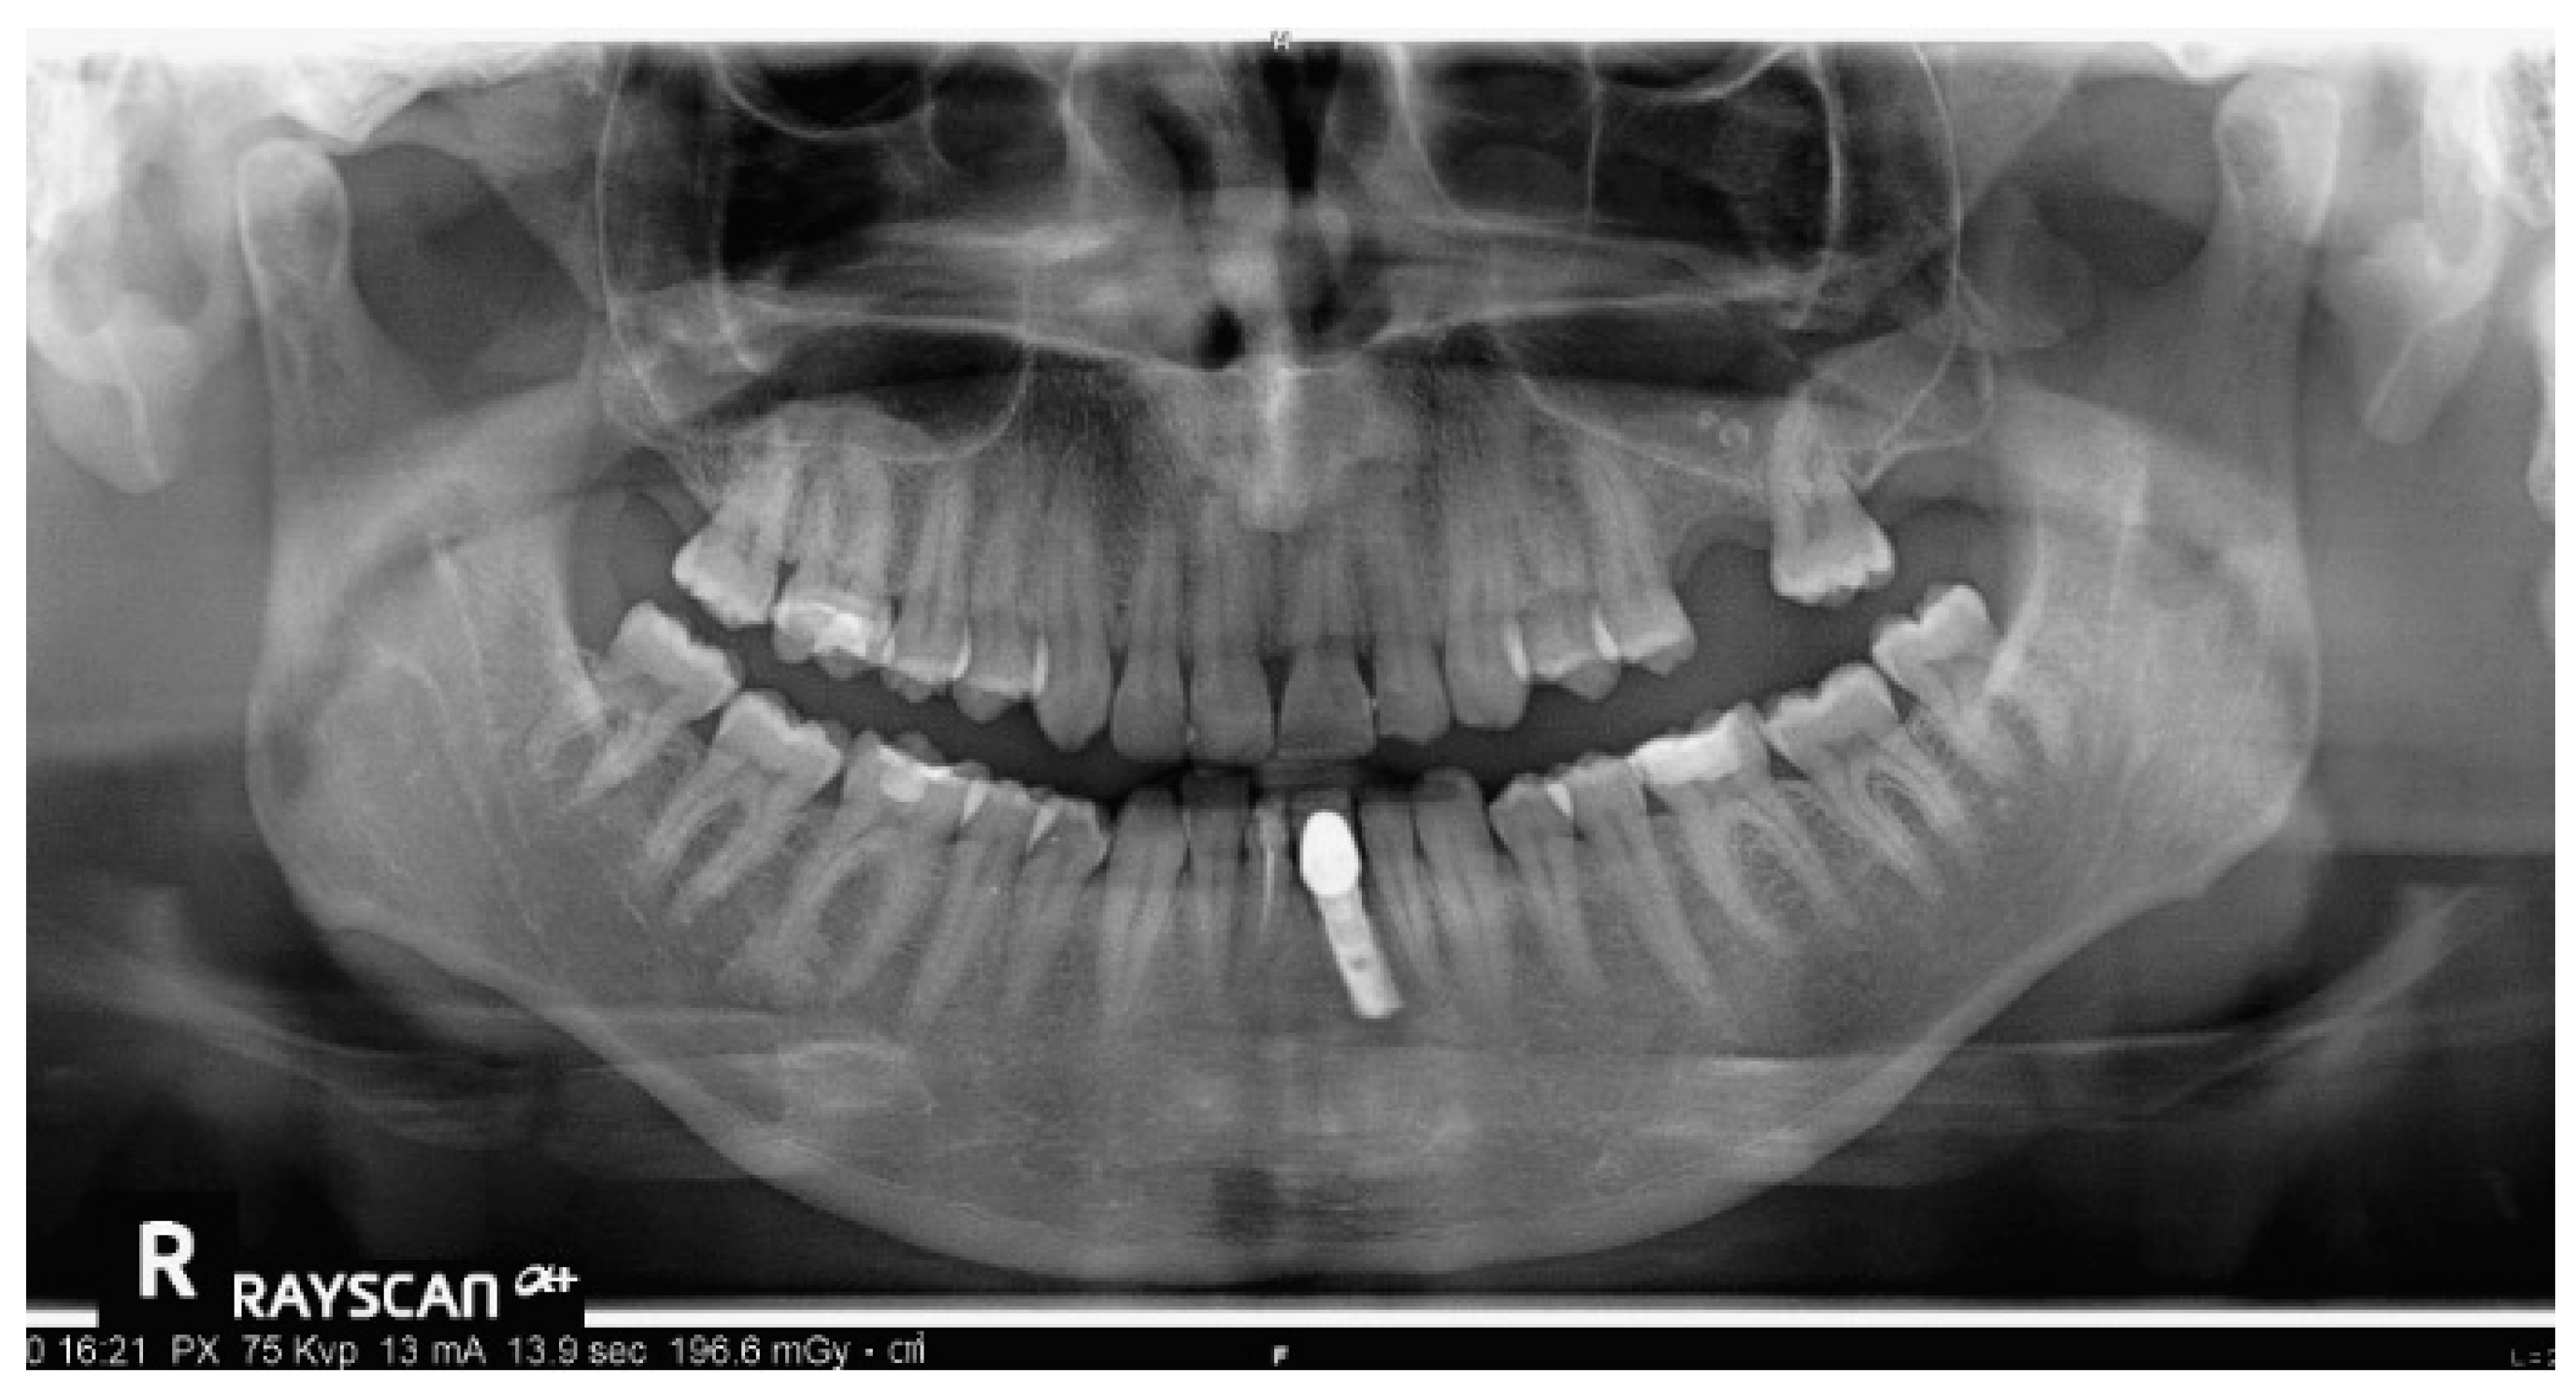

Intraoral views are shown in Figure 25, and Figure 26 reports orthopantomography: the absence of element 26, implant-prosthesis of element 31, and condylar asymmetry. It was indicated to investigate the diagnostic with an X-ray of elements 3.6 and 4.6.

Figure 26. Absence of element 26, implant-prosthesis of element 31, and condylar asymmetry. It was indicated to investigate the diagnostic with an X-ray of elements 36 and 46.